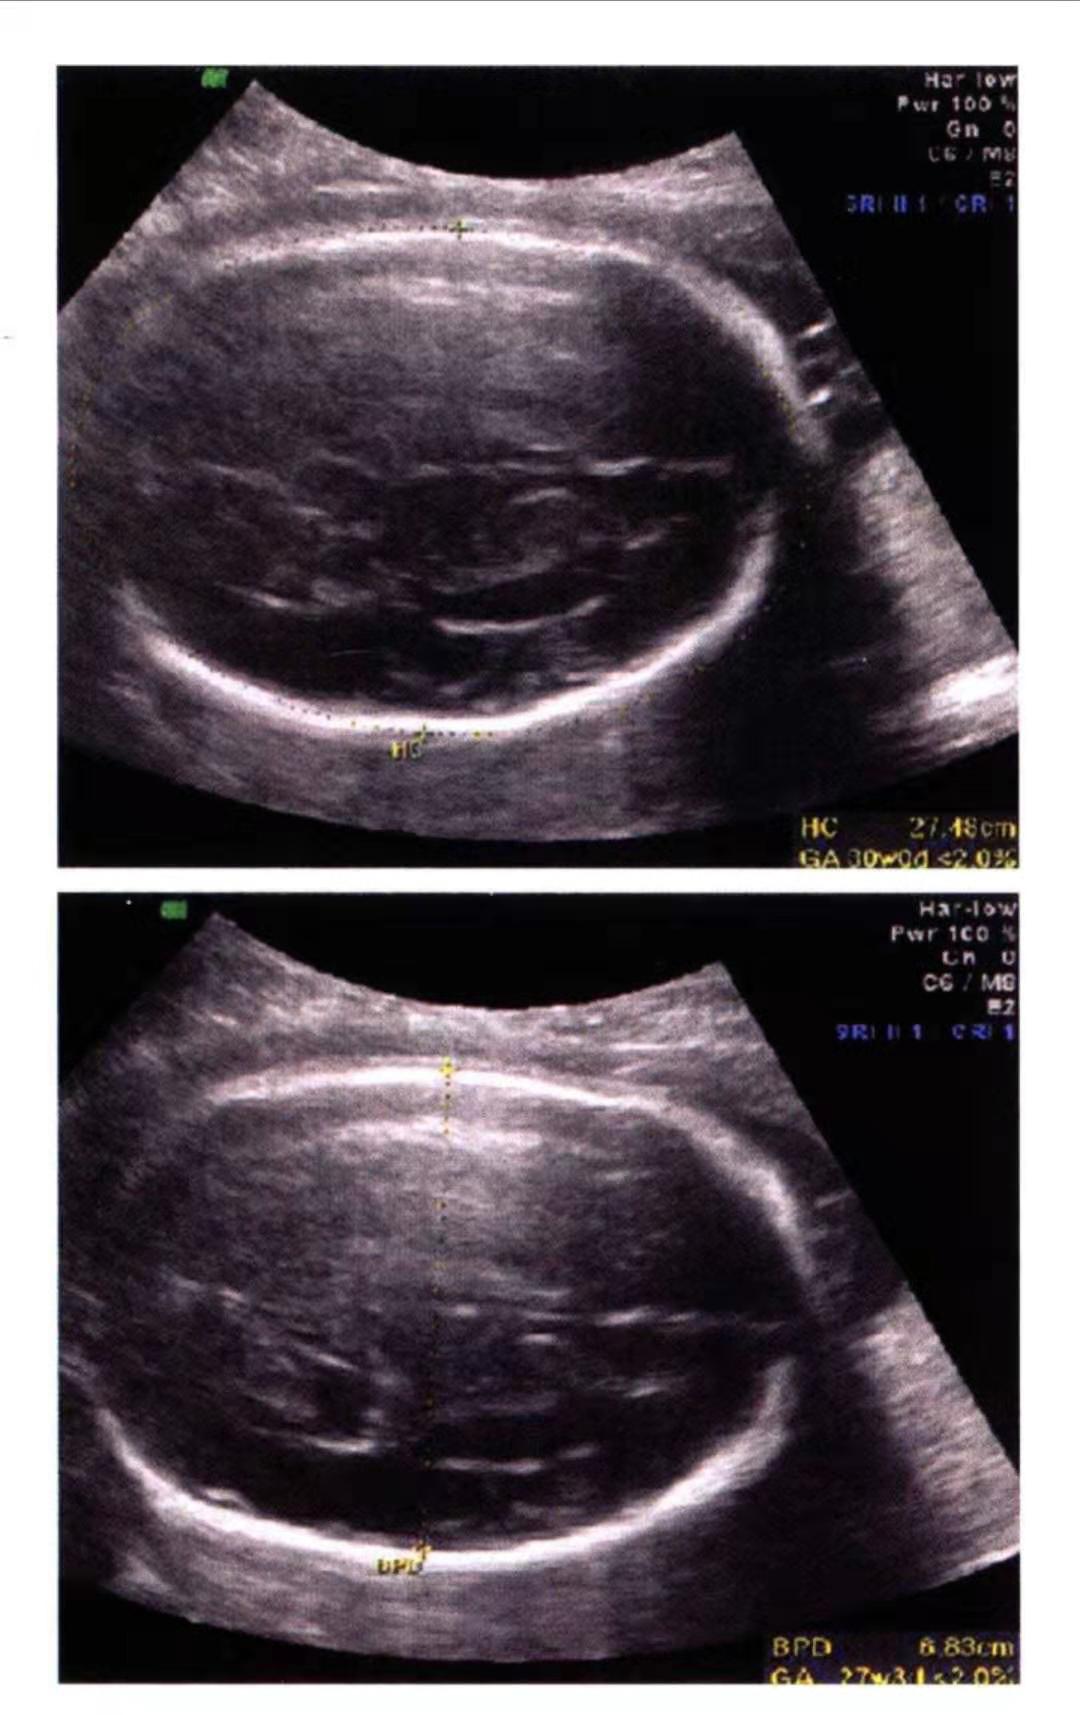

这一做倒好,B超做出来双顶径就83mm,股骨长70mm,腹围340mm,头围300mm。双顶径才83mm,头围才300mm,有没有搞错呀,明明上次孕38周的时候,双顶径就有85mm,头围313mm,为什么养了两周双顶径反而小了。医生当时给出的答案就是有可能是B超误差或者是入盆引起的(入盆可以导致骨缝重叠)。

作为一个合格的产科医生,当看到一个孕40周,而双顶径却只有83mm的胎儿肯定会引起重视,其中一点就是会不会是小头畸形,毕竟除了双顶径和头围,其他都在正常范围。下面我粗略的来讲一下小头畸形。